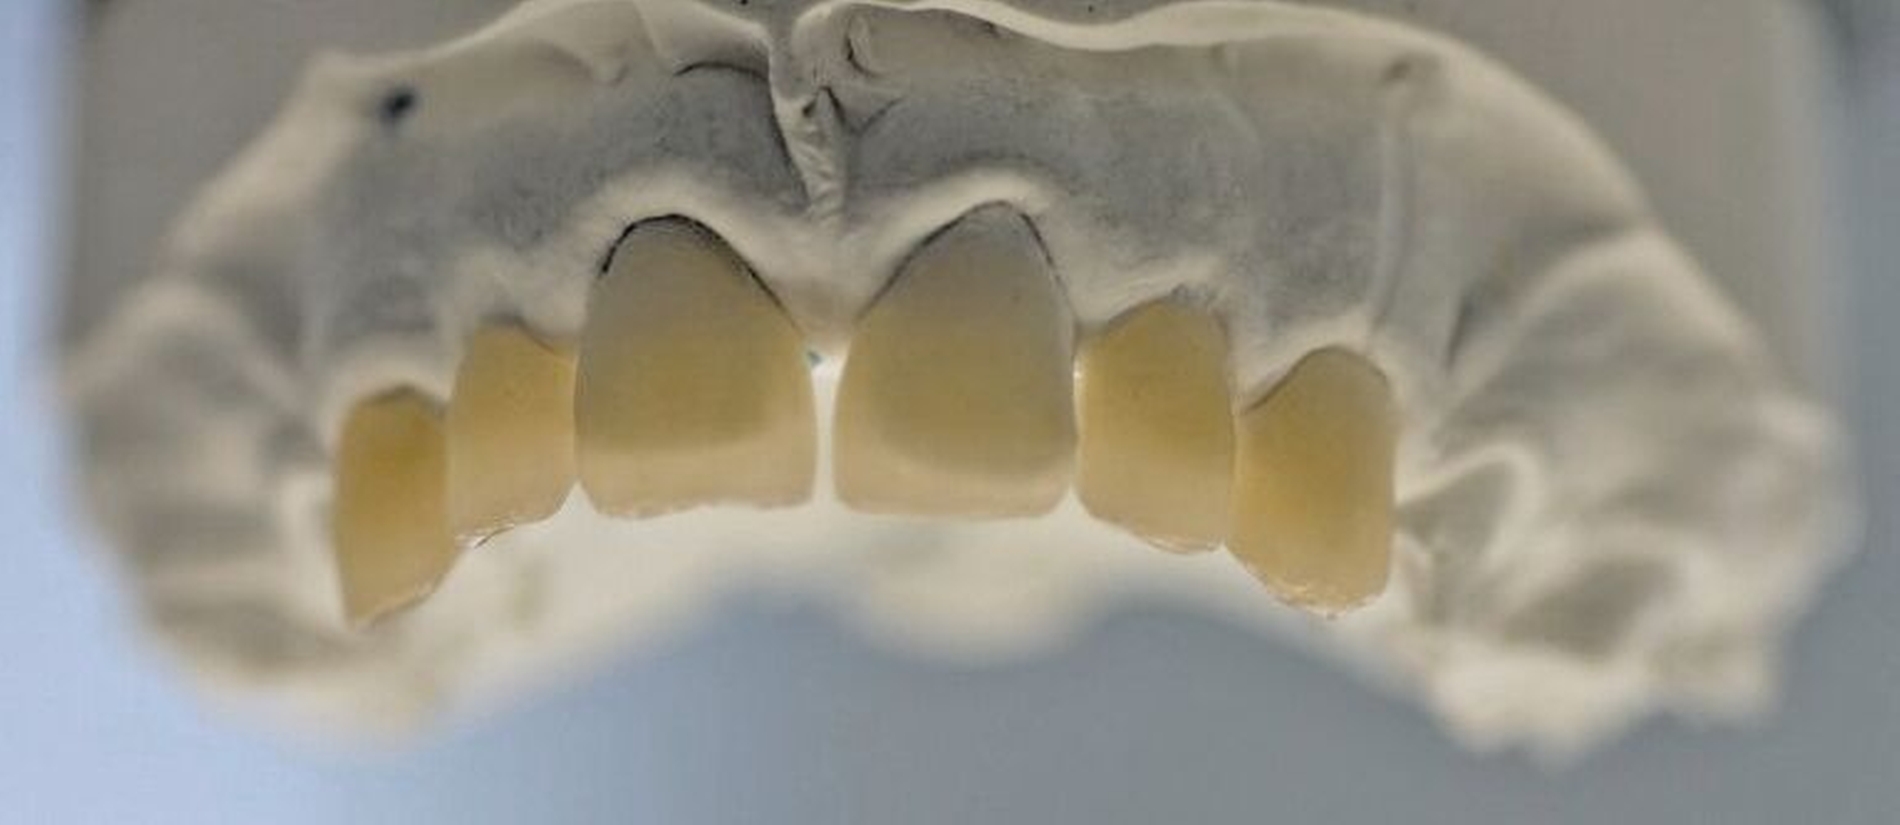

Nach der Extraktion von Zahn 64 wurden die übrigen kariösen Milchzähne nach Konditionierung (Prime&Bond NT, Dentsply Sirona) mit Kompomer (Dyract extra, Dentsply Sirona) versorgt. Für die Frontzahnbehandlung wurde zunächst ein Wax-up auf Situationsmodellen erstellt (Abbildung 3), anschließend eine Silikonformhilfe angefertigt. Nach Reinigung und 3-Schritt-Etch-and-Rinse-Konditionierung (OptiBond FL, Kerr) unter relativer Trockenlegung wurden die Zähne in Mehrschichttechnik mit einem Mikrohybrid-Komposit (Herculite XRV, Kerr) versorgt. Die Seitenzähne wurden wegen des ausgeprägten Würgereizes unter absoluter Trockenlegung mit fließfähigem Komposit (Tetric flow, Ivoclar Vivadent) temporär rekonstruiert (Abbildung 4).